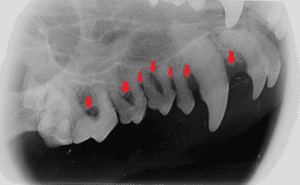

Figure 3. Picture of the right maxilla of a dog showing teeth with advanced periodontal disease. Note the advanced calculus and severe gingival inflammation.

Figure 4. Radiograph of the right maxilla of the same dog as in Figure 3 with advanced periodontal disease. Note the severe bone loss (>50%) and furcation exposure.